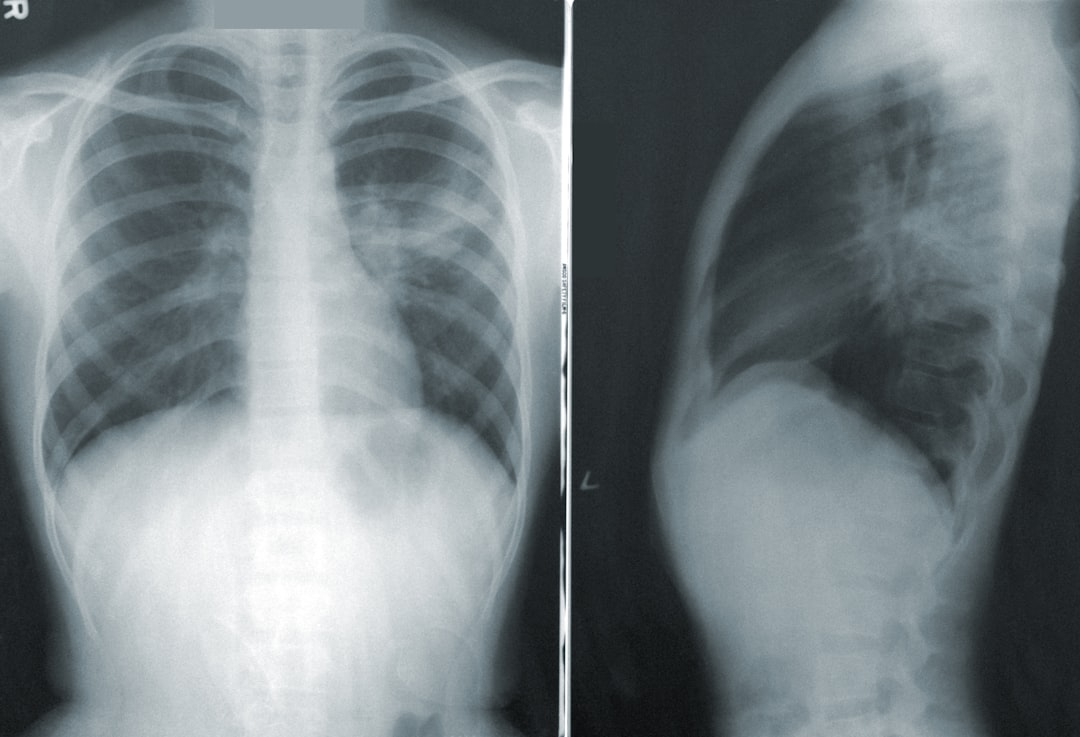

폐렴은 염증 상태뿐만 아니라 폐에 세균이나 바이러스가 침투하여 생기는 질병이죠. 일반적으로 성인은 평균 5일에서 10일 정도 병원에서 치료를 받게 됩니다. 하지만 이 입원기간은 나이, 건강 상태, 그리고 면역력에 따라 상당히 차이가 날 수 있습니다. 특히 노인 폐렴 입원기간은 더 길어질 수 있으며, 심한 경우에는 2주 이상도 소요될 수 있습니다. 이러한 정보는 궁극적으로 우리 자신과 사랑하는 사람들을 더욱 잘 이해하고 준비하는 데 도움이 됩니다.

반면에, 성인들은 여러 건강 문제를 겪고 있을 수 있어서 치료방법은 조금 더 복잡해질 수 있습니다. 성인 폐렴 입원기간은 영향 요인에 따라 달라지지만 평균적으로는 5일에서 10일 정도입니다. 입원 치료를 받는 동안 주로 항생제를 처방받고, 경우에 따라 산소 치료가 필요하기도 합니다. 이러한 치료 방식은 각자의 상황에 따라 다르게 적용될 수 있습니다.

노인은 면역체계가 약해져 있어서 폐렴 입원기간이 일반적으로 더 길어질 수 있습니다. 제 할아버지가 겪었던 폐렴은 정말 기나긴 싸움이었죠. 노인 폐렴 입원기간이 보통 1주에서 2주까지 늘어난다는 것을 알게 된 것은 그때였습니다. 그 경험은 저와 가족에게 큰 교훈이 되었습니다.진단과 치료가 얼마나 중요한지, 더구나 노인에게는 더욱 그러하다는 것을 몸소 깨달았습니다.